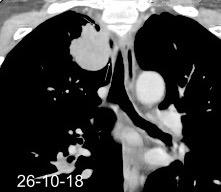

Marzo 2014: Perforación longitudinal distal secundaria a episodio de vómito (síndrome de Boerhaave). Derrame pleural izdo. que evoluciona a empiema.

Wang C-T et al. Tension hydropneumothorax in a Boerhaave syndrome patient: A case report . World J Emerg Med, 2021. Katabathina V et al. Nonvascular, nontraumatic mediastinal emergencies in adults:a comprehensive review of imaging findings. Radiographics. 2011.